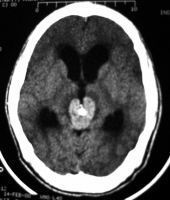

Pineal Germinoma

Paediatric Pt group.

CT Fx: Nonenhanced CT - slightly hyperattenuating mass with areas of Ca++. Contrast-enhanced - homogeneous / intense enhancement.

MRI Fx: Usu. ISO-intense to grey matter on T1 and T2. Shows homogenous / intense enhancement.

T1+Gad sagittal demonstrating enhancing pineal germinoma